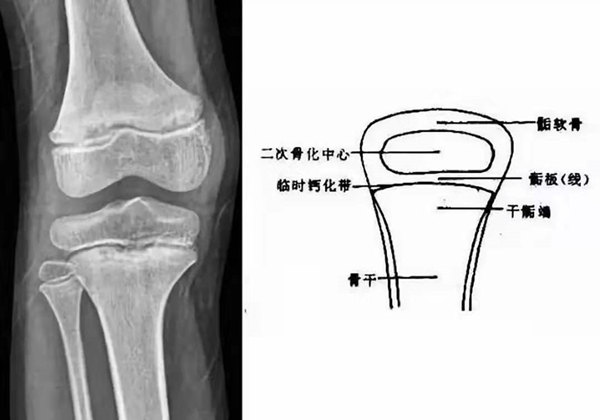

我們都知道,人體的高矮是由骨骼的生長(zhǎng)發(fā)育決定的,特別是下肢長(zhǎng)骨。長(zhǎng)骨呈長(zhǎng)管狀,在長(zhǎng)骨的兩端有一種專(zhuān)管骨骼生長(zhǎng)的骺軟骨,它與干骺端之間有一盤(pán)狀軟骨結(jié)構(gòu)稱為骺板(線),在幼兒的X光片上表現(xiàn)為一條較寬的透光帶。 (見(jiàn)下圖)

未成年時(shí)隨著年齡的增加骺軟骨端不斷骨化,骨骼就不斷增長(zhǎng)。當(dāng)骨骺線完全閉合時(shí)骨骼就停止生長(zhǎng),個(gè)子也就不再增長(zhǎng)了。一般骨骺端完全閉合的年齡是18~20歲左右。